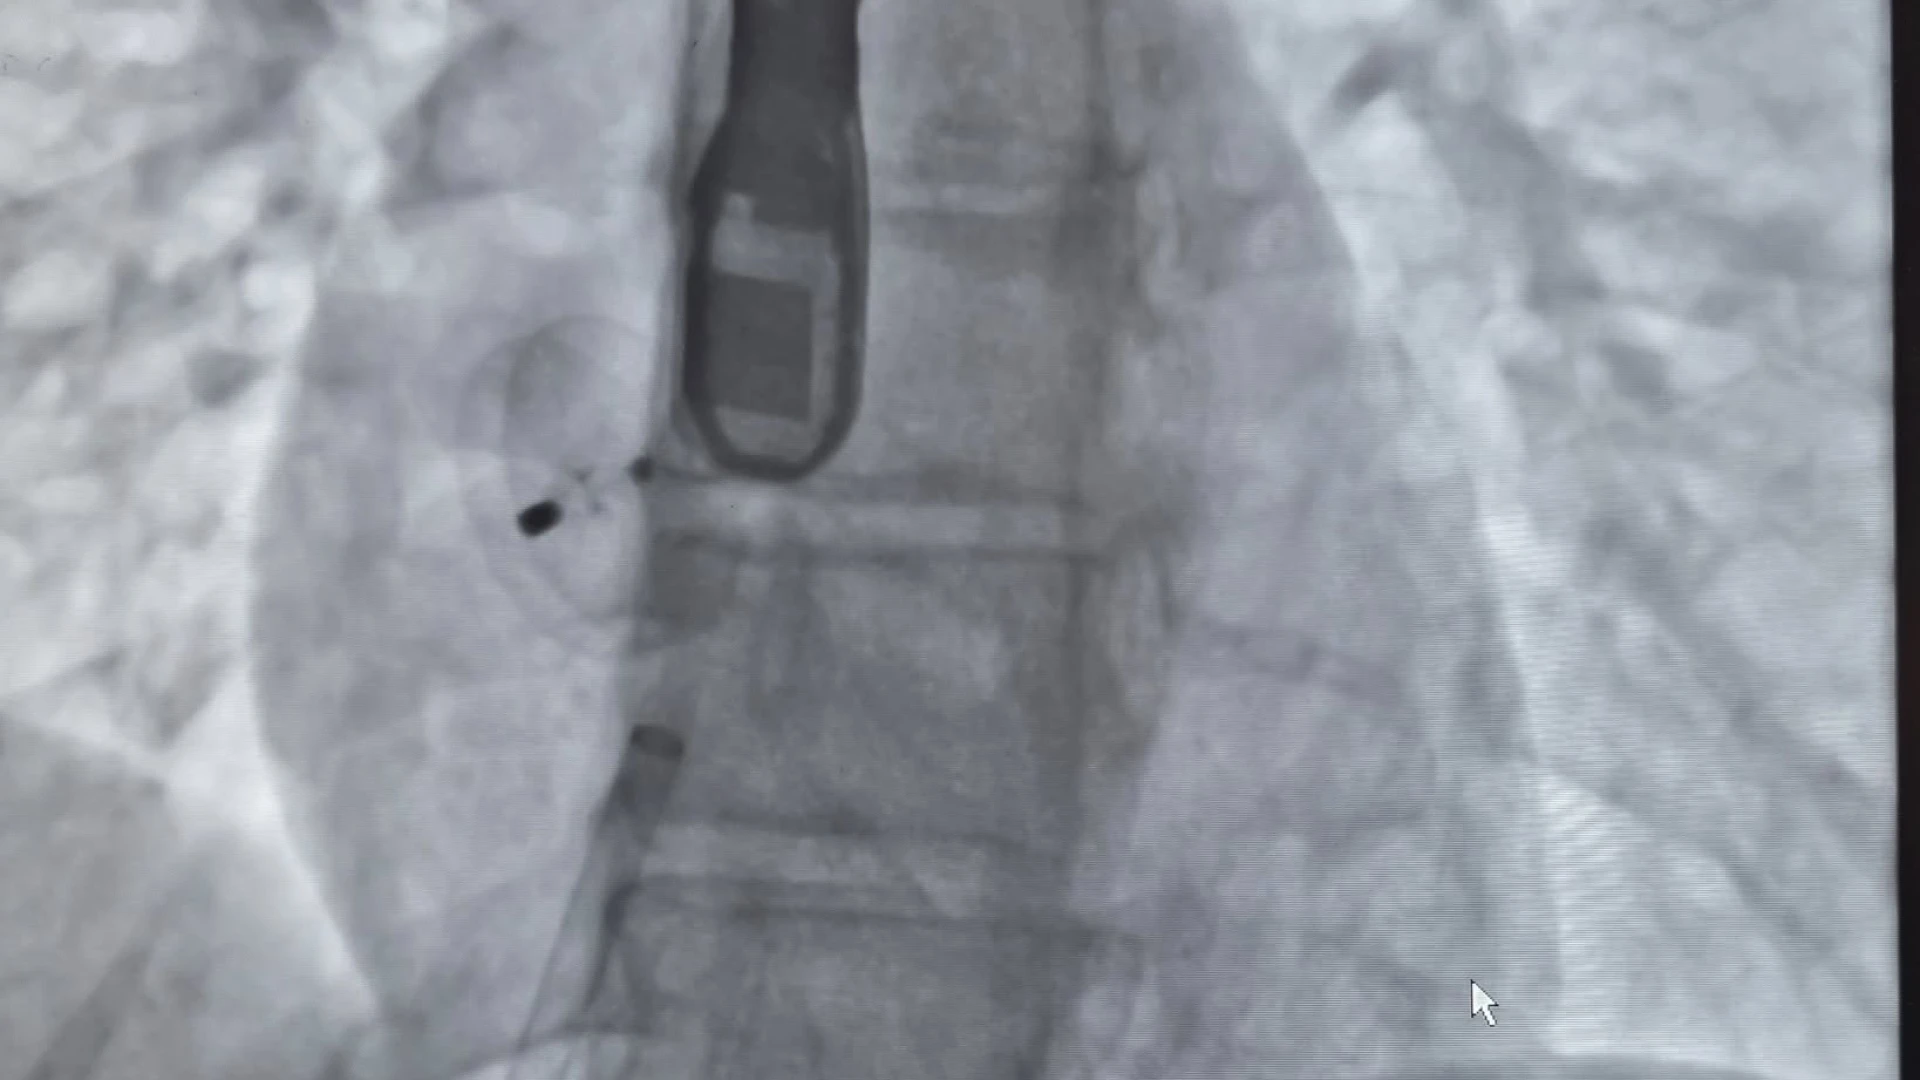

Procedure interventistiche di rilievo anche al P.O. San Timoteo di Termoli dove, in questi giorni, sono state effettuate due chiusure per via percutanea di Forami Ovali Pervi (PFO) in due giovani pazienti con precedenti episodi di ischemia cerebrale. Si tratta di interventi mini-invasivi che mirano a chiudere una comunicazione anomala tra i due atri del cuore, spesso identificata come un'apertura residua del forame ovale presente nel periodo fetale. Si eseguono mediante l'introduzione di un dispositivo, simile a un ombrellino, attraverso un catetere, generalmente introdotto attraverso la vena femorale.